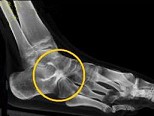

- 男,28岁, 踝部肿痛,结合图像, 最可